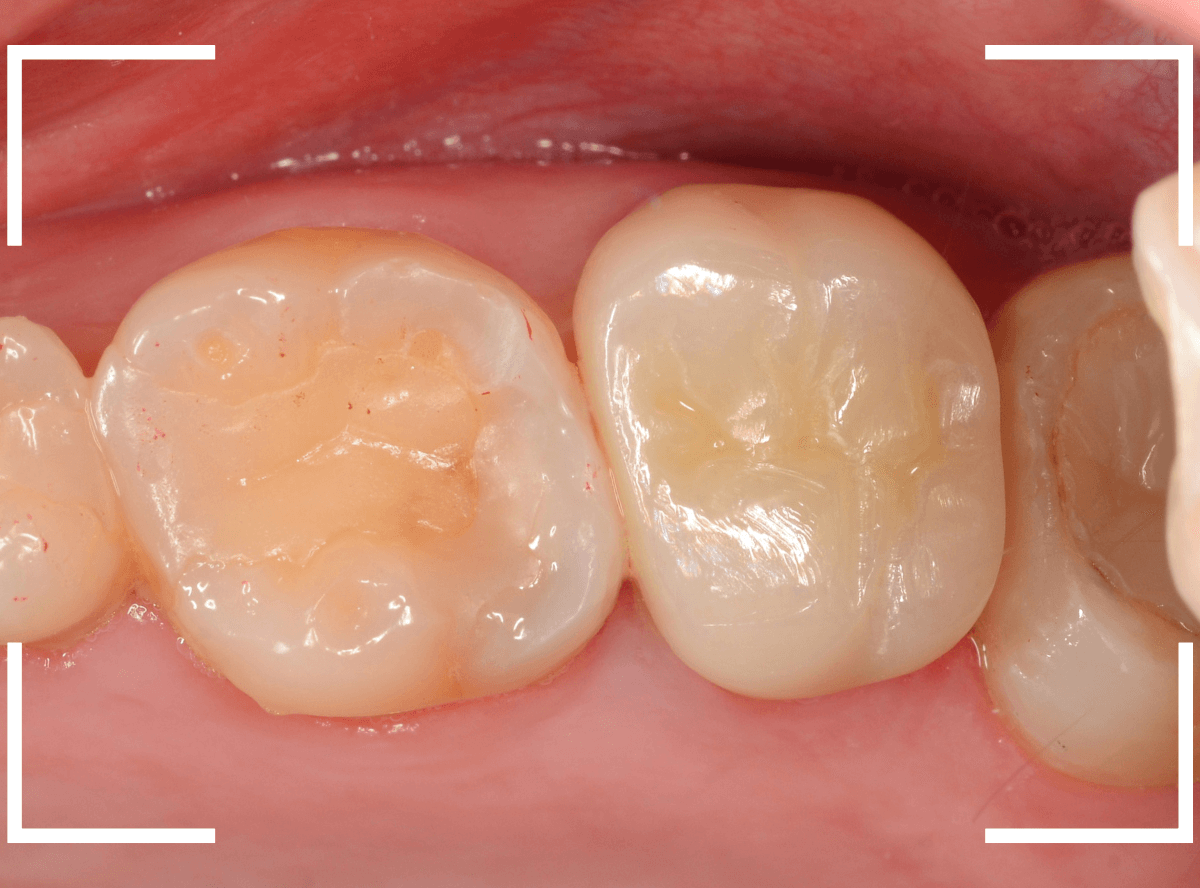

set後の写真です。

患者さんにも満足していただける仕上がりになりました。

治療前後の比較写真になります。